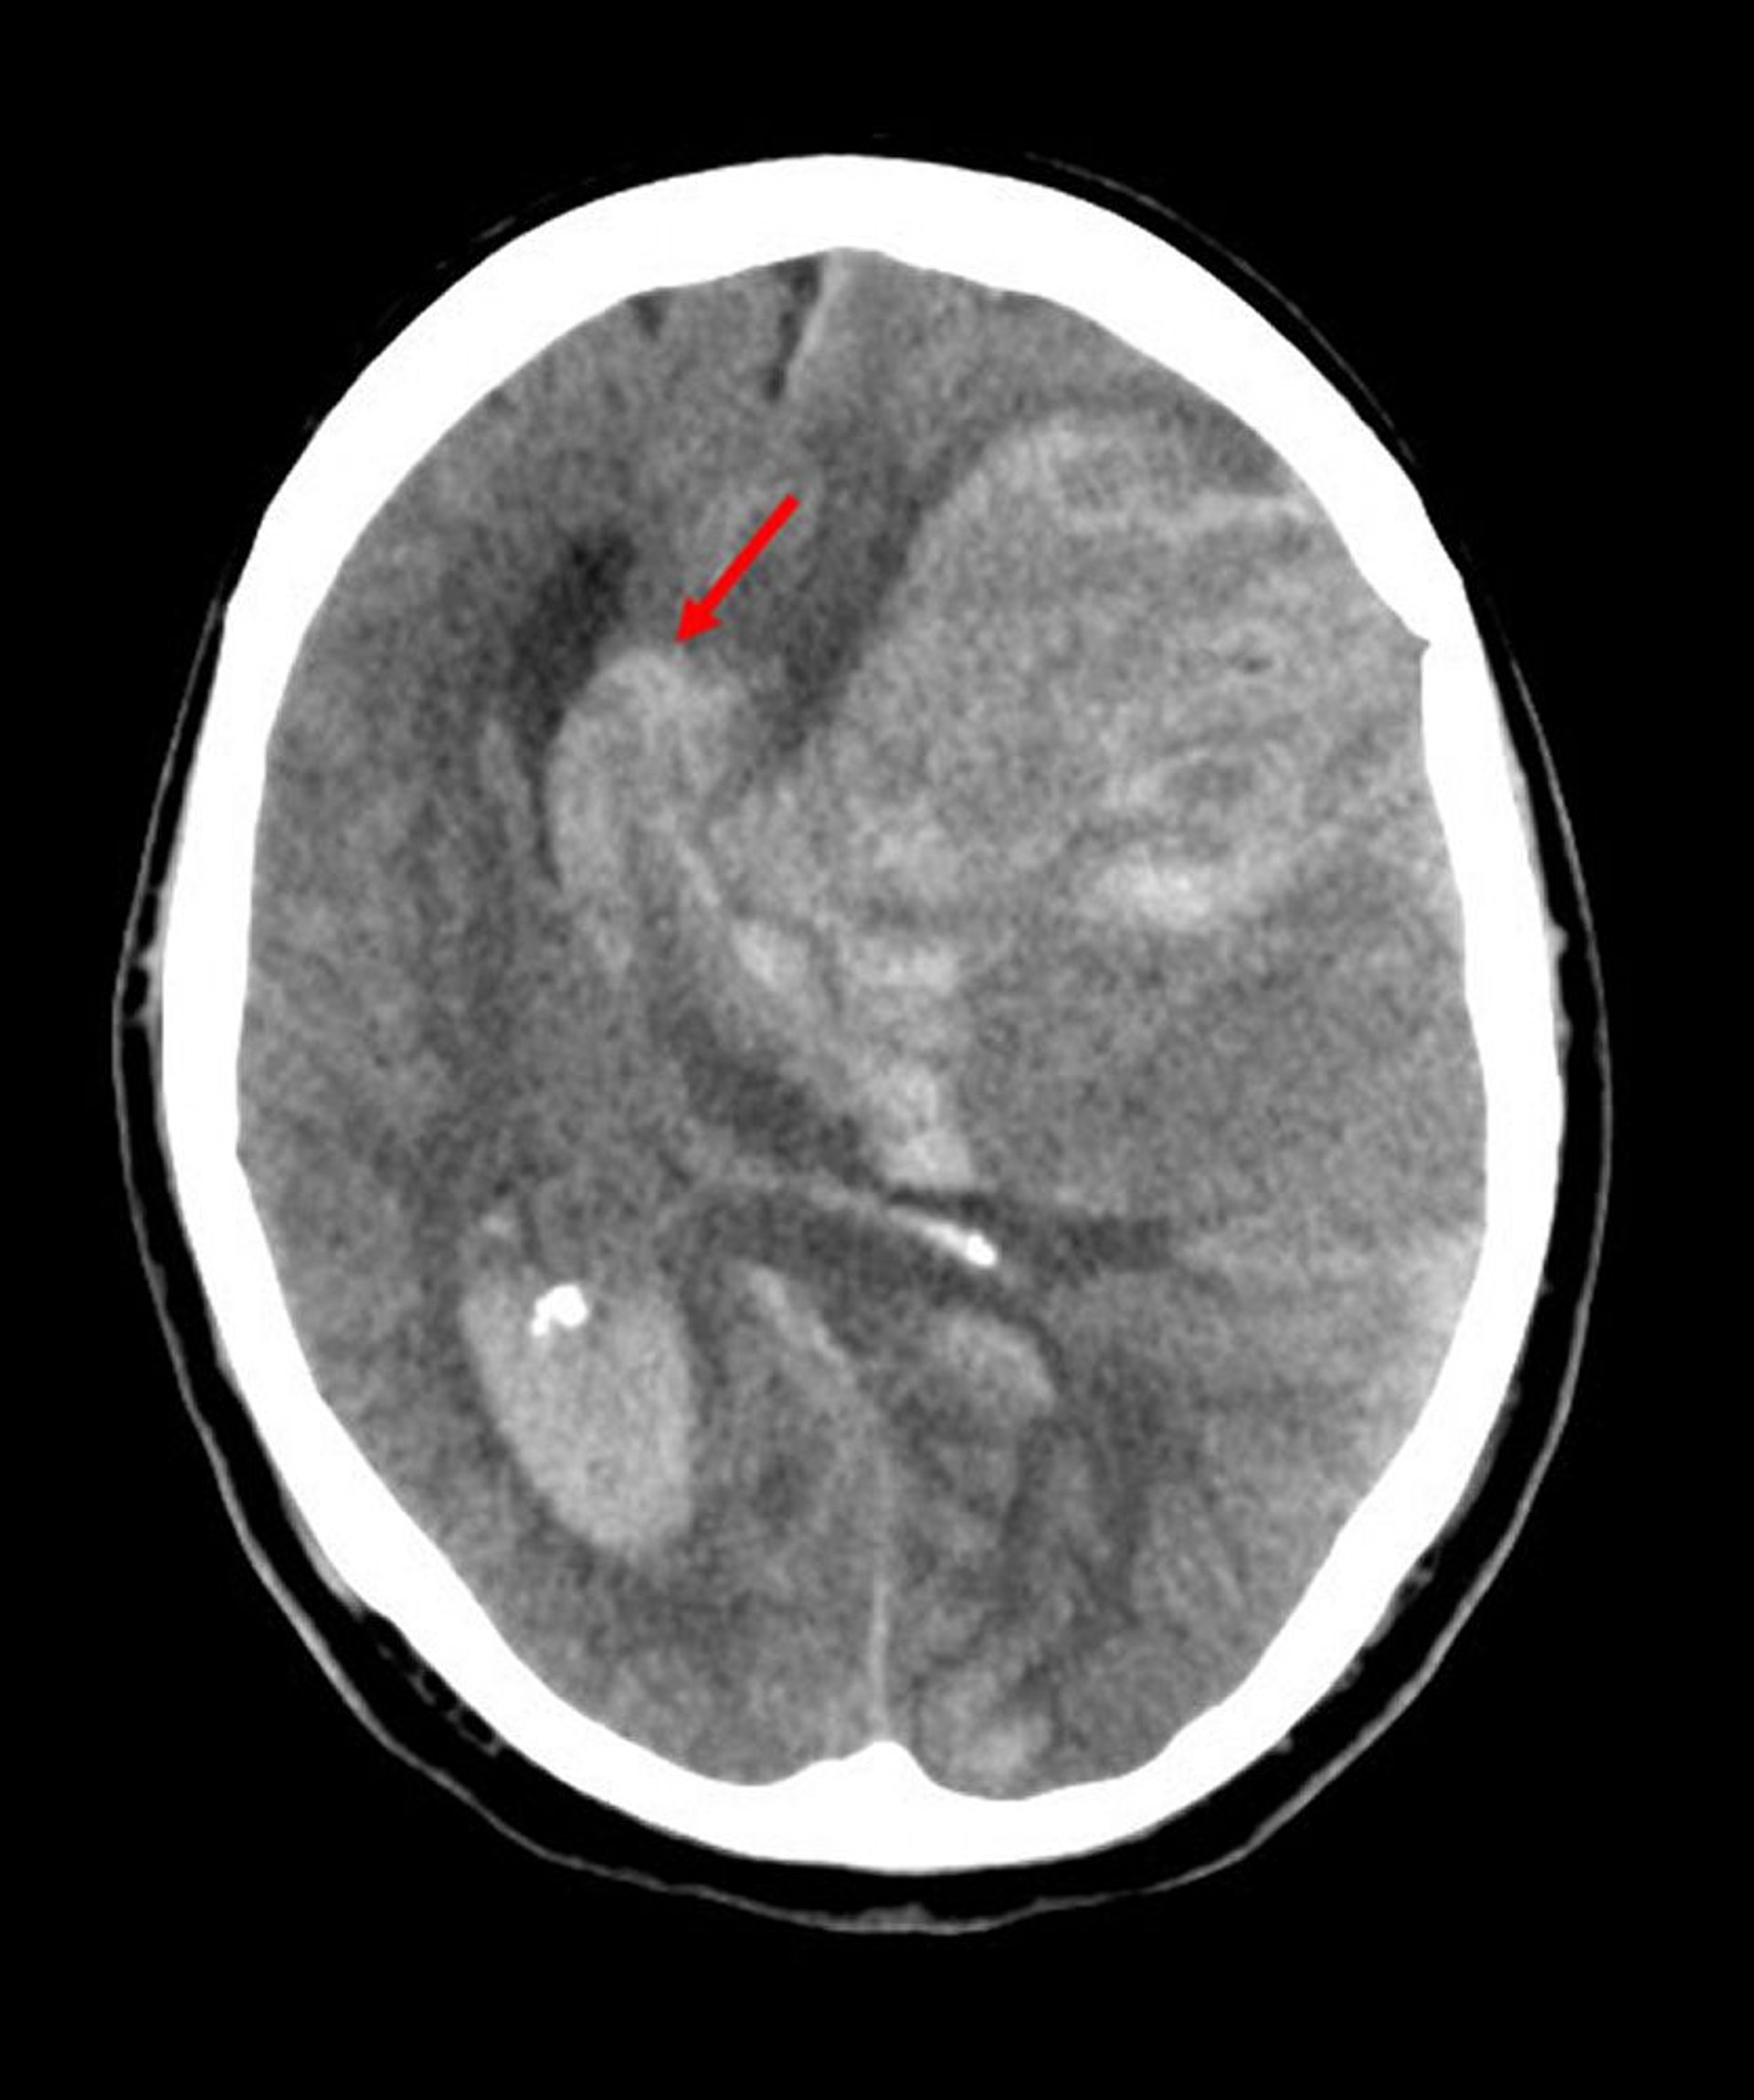

Субфальцинова грижа

Subfalcine herniation is the most common type of cerebral herniation. In this image, the left brain has herniated under the free edge of the falx cerebri (arrow) because hemorrhage from an infarct in the middle cerebral artery has increased intracerebral pressure.